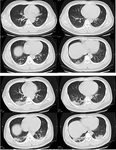

Поперечная компьютерная томография 32-летнего мужчины показывает затемнение по типу матового стекла и уплотнение в нижней доле правого легкого возле плевры в 1-й день после появления симптомов (верхний снимок), а также двусторонние затемнения и консолидацию по типу матового стекла на 7-й день после появления симптомов